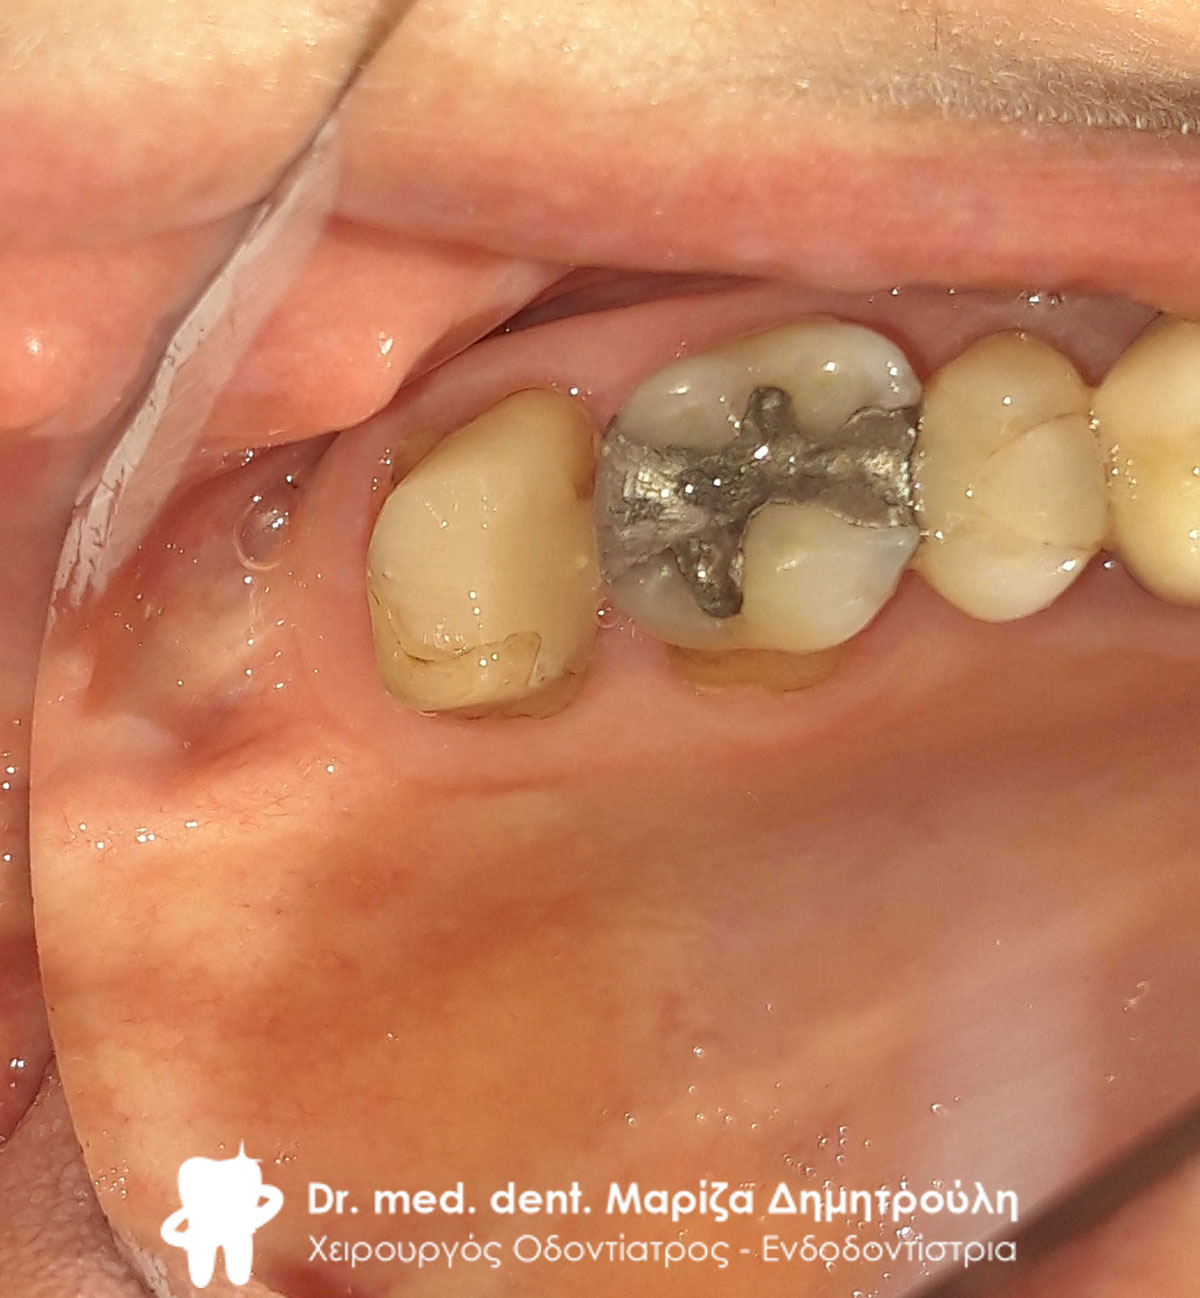

Περιστατικό – Ολοκεραμική στεφάνη / θήκη ζιρκονίου στην αριστερή πλευρά της κάτω γνάθου

Ο ασθενής είχε ένα παλιό μεγάλο σπασμένο σφράγισμα στον κάτω γομφίο. Το δόντι αρχικά απονευρώθηκε και στη συνέχεια καλύφθηκε με ολοκεραμική θήκη ζιρκονίου.

Αρχική κλινική εικόνα του δοντιού με το παλιό σπασμένο σφράγισμα

Κλινική εικόνα της ανασύστασης του δοντιού

Τελική εικόνα της ολοκεραμικής θήκης